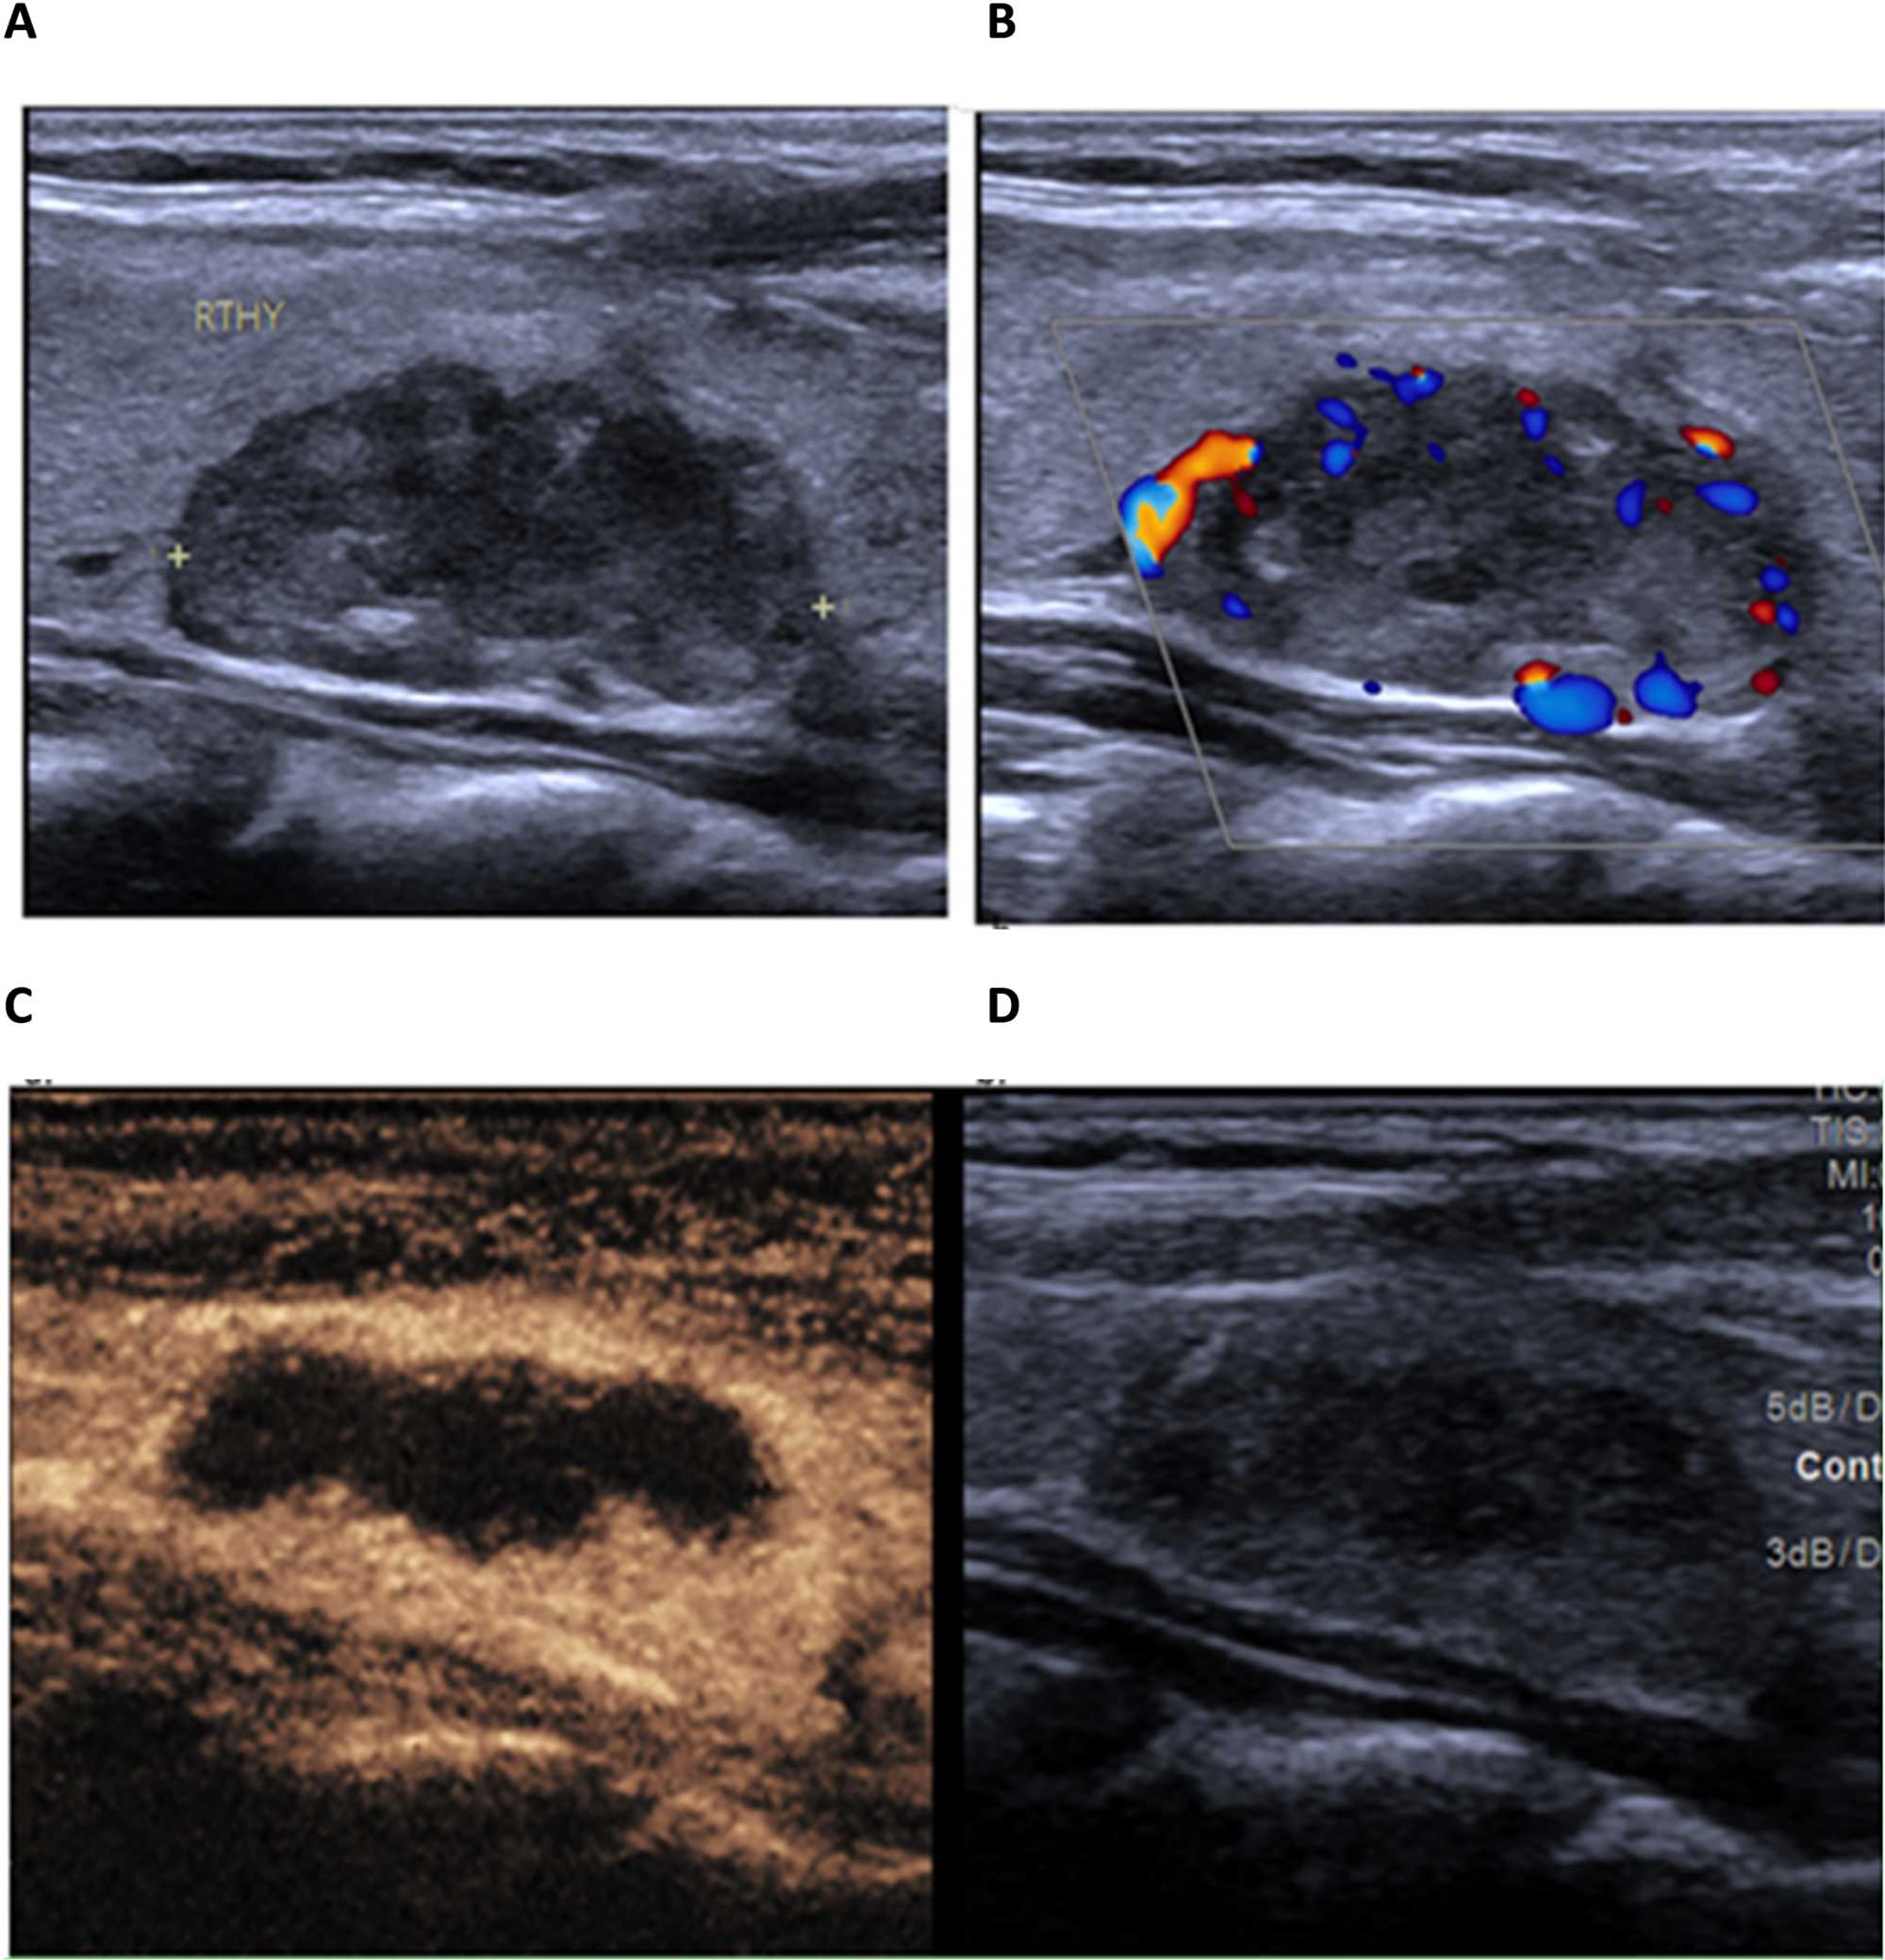

The primary outcome of this study was nodule inactivation following RFA. Of the 72 patients, 51 (70.8%) had complete nodule inactivation, while 21 (29.2%) had partial inactivation. Figure 2 shows nodule images of 2 patients before and after RFA. The two groups of patients had no significant differences in terms of age, gender, nodular diameter and volume (all p > 0.05). Those with complete inactivation had more calcification (p = 0.040), while those with partial inactivation had more vascularity (p < 0.001). Table 2. Analysis of changes in thyroid hormone levels between the two groups over a 6-months period showed no significant difference, although slight increase in TSH levels were seen within groups over the same period. Table 3. Figures 2-4 show sonographic images of a benign nodule pre RFA, a partially inactivated nodule and a completely inactivated nodule respectively.

Figure 4. Follow up after 9 months. (A) A coarse and heterogeneous thyroid parenchyma with a small ill-defined lesion solid lesion with tiny linear calcification in the left lobe (B). CEUS shows an enhanced thyroid parenchyma with unenhanced tiny area in the right isthma. (C, D) These changes suggest complete inactivation.